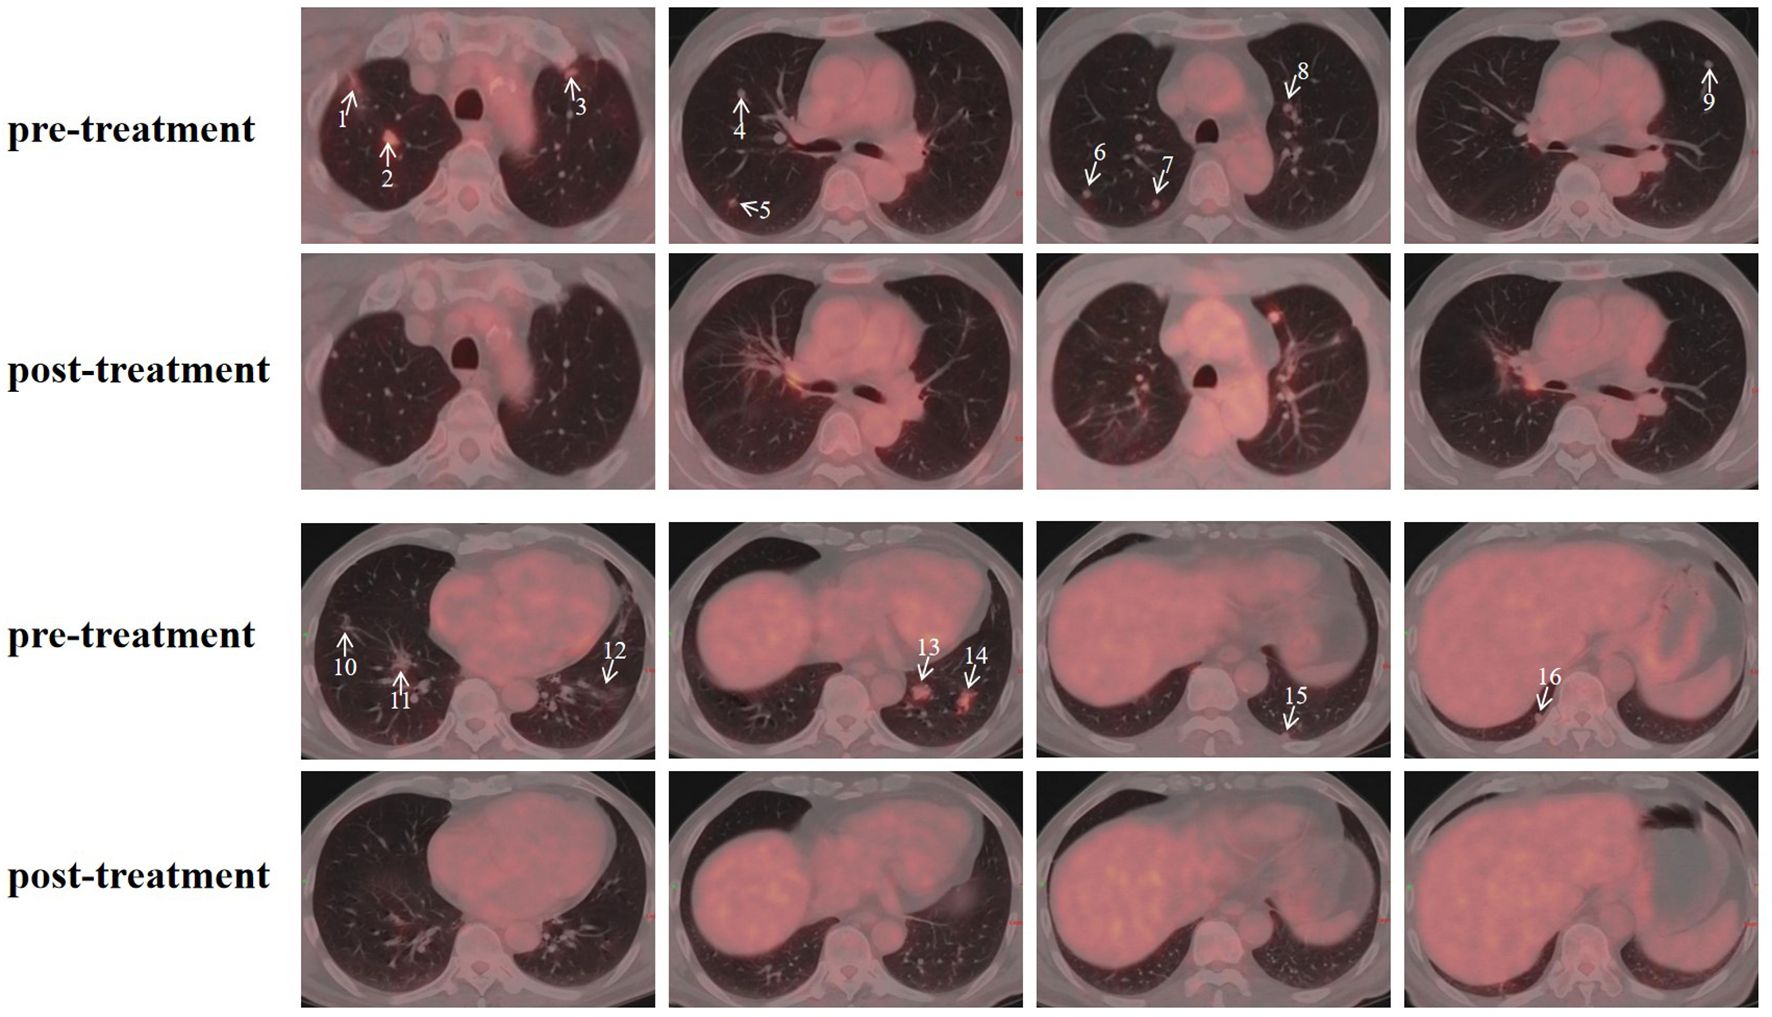

Adenoid Cystic Carcinoma (ACC) is characterized by its aggressive nature, high propensity for perineural invasion, and significant risk of distant metastasis, particularly to the lungs. Therapeutic options for locally advanced or metastatic ACC are limited, and conventional radiotherapy is often constrained by dose limitations for multifocal disease, leading to inadequate treatment. A 54-year-old male ACC patient, who had recurred after three prior surgeries, presented with PET/CT-confirmed bilateral cervical lymph node and multiple bilateral pulmonary metastases. Given the multifocal metastases and the critical need for sparing organs at risk (lungs, heart, esophagus), which rendered photon radiotherapy unable to meet the required dose constraints, proton therapy was employed with the following dose prescriptions: for pulmonary metastases: CTV 50 Gy(RBE) in 15 fractions, GTV 60 Gy(RBE) in 15 fractions; for the cervical lesion: GTVnd 70 Gy(RBE) in 28 fractions, CTVnd 66 Gy(RBE) in 28 fractions, CTV 50.4 Gy(RBE) in 28 fractions. Follow-up PET/CT post-treatment demonstrated complete resolution of some bilateral pulmonary metastases, with marked reduction in size and decreased metabolism in the remaining nodules. The metastatic cervical lymph nodes also showed reduced volume and metabolic activity. No adverse events exceeding Grade 2 occurred during the treatment course. This case demonstrates that proton therapy is highly suitable for multifocal ACC metastases, especially multiple small pulmonary nodules. Through its precise dose delivery, it enables high-dose irradiation (GTV 60–70 Gy(RBE)) to targets while significantly sparing normal organs. This approach represents a viable strategy for complex cases where conventional radiotherapy is contraindicated. It aims to delay disease progression and achieve organ preservation in refractory ACC.